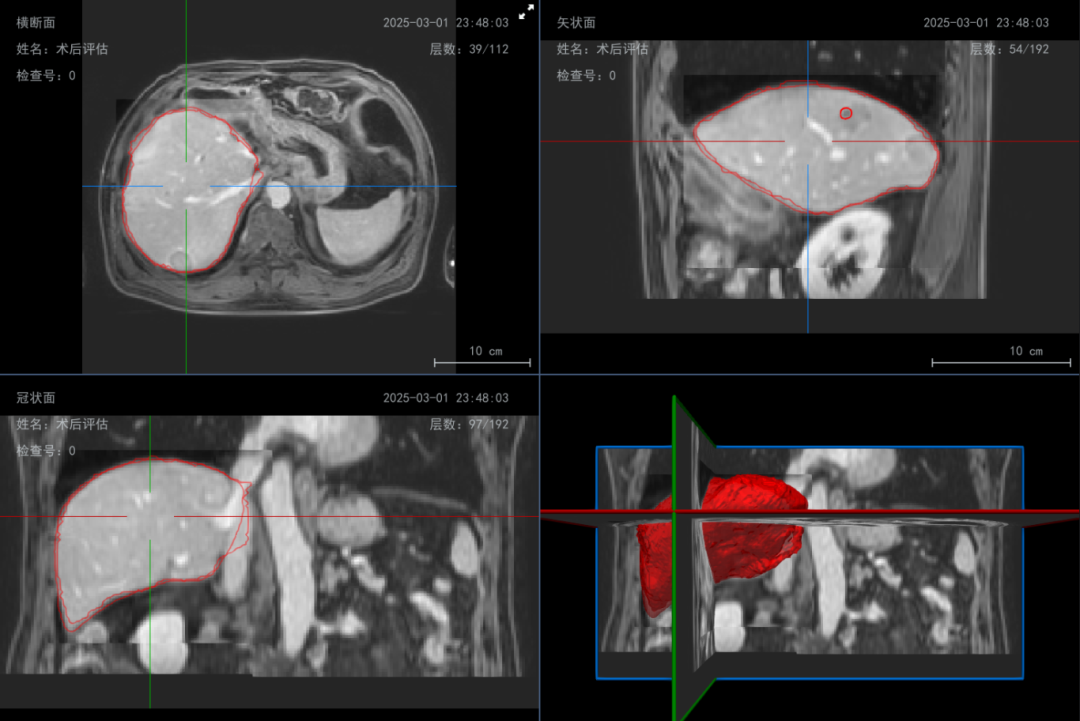

在术后,通过与术前三维规划方案进行自动配准与多平面同步对比分析。系统可在横断、矢状、冠状视图中清晰标注并量化显示实际消融区域与术前目标区域的匹配度,支持医生从空间覆盖完整性和消融均匀性等维度进行综合评价。

至此,德文医学监测消融评估系统通过“术前AI规划穿刺路径—术中双频能量精准调控与实时可视导航—术后即时影像评估”,构建了覆盖肿瘤治疗全流程的精准闭环。